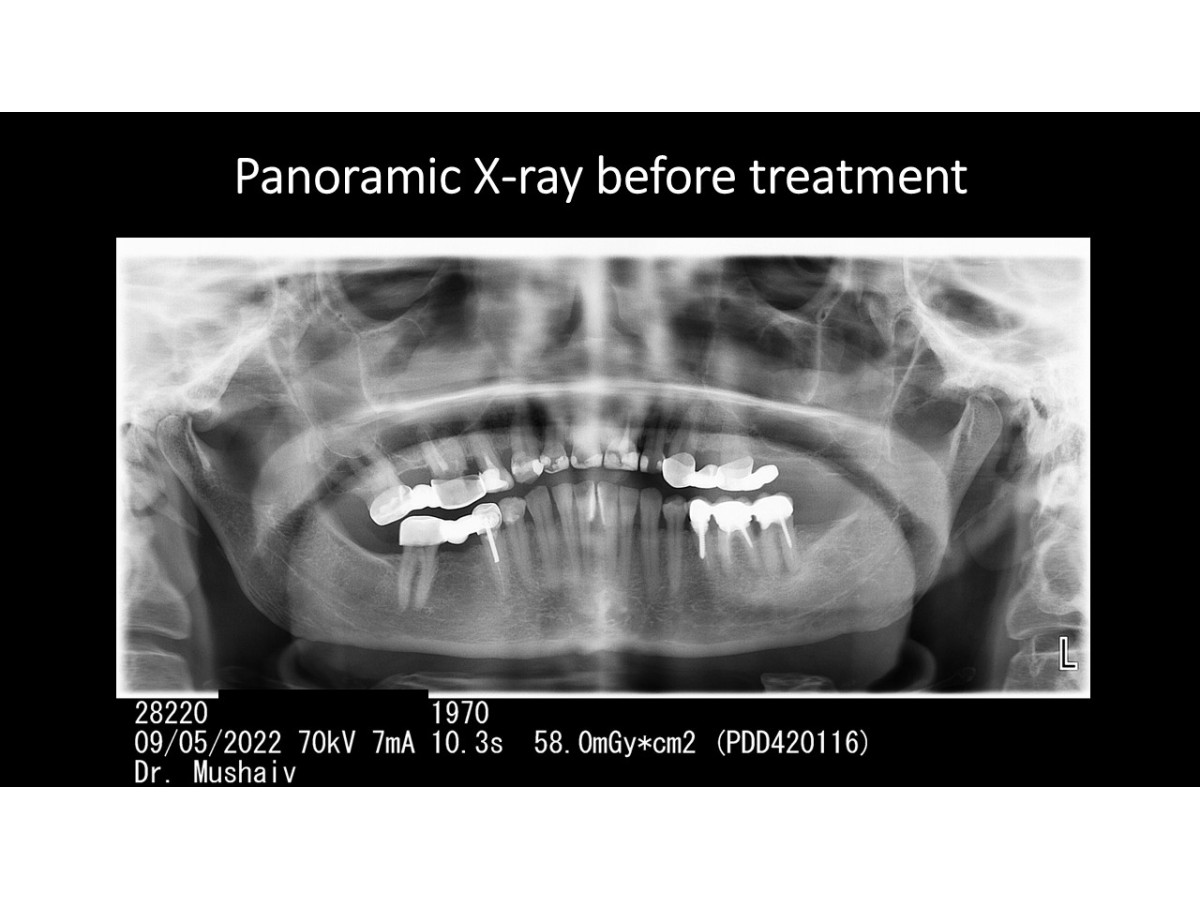

Clinical case: Sinus lifting with immediate implantation, bone augmentation, soft tissue monitoring

Dentist: DDS PhD Ilia Mushayev/Sidhedent, DMi (Israel)